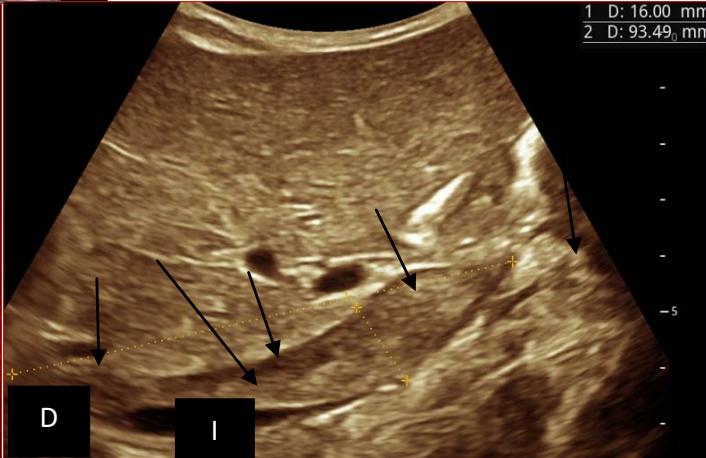

Figure 5: Abdominopelvic ultrasound control after 6 courses of chemotherapy in the same 3 year old patient with a ruptured left renal nephroblastoma; Images A, F, G, and H: show regression of the solid, endo and exo renal, left nephroblastoma mass treated with 6 courses of chemotherapy (current volume 430 ml vs) Images: B, C, and: show persistence of thrombotic permeation pan vena cava and ipsilateral renal. Image E: shows a volumetric regression of the intra-lesional hematic collection, at the tumor rupture estimated at 34.49 ml VS, Image I: represents the right kidney in B mode which is of normal echoculture. Source: Dr. Frederick Tshibasu Tshienda database.